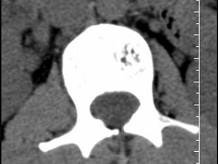

问题 根据所提供的图像,选择最可能的诊断 ( )

选项 A、退行性变 B、骨质疏松 C、多发性骨转移 D、骨血管瘤 E、骨结核

答案 D